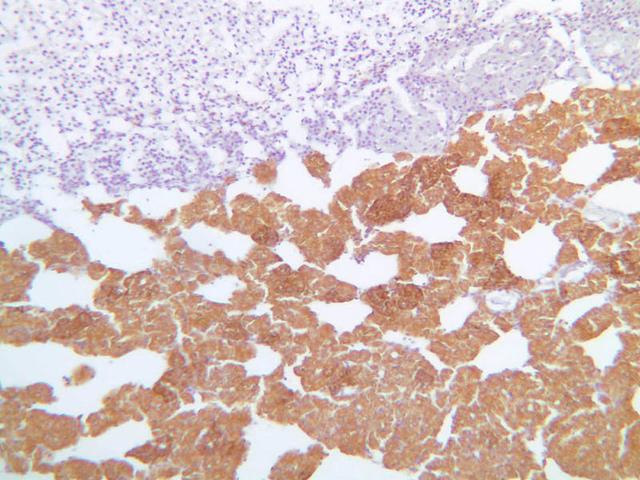

The adrenal gland (slide B-59, H&E [2.5x-labeled, 10x-labeled, 20x, 40x-labeled] [2.5x, 10x-labeled, 20x, 40x]; B-60, H&E [2.5x-labeled, 10x, 20x, 40x]; B-62, H&E [10x, 20x, 40x] [2.5x, 10x]) is a composite organ consisting of two functionally, structurally and embryologically different parts—an outer cortex and an inner medulla. Observe the gland at low power. Find the loosely organized tissue that comprises the medulla and the partially-separated columns of cells that make up the cortex. Scan the capsule and the tissue around it, looking for nerves and blood vessels. Study the pattern of cortical vasculature. In a pattern similar to that seen in the pars distalis of the pituitary, sinusoids run along the edges of columns or cords of cells. Owing to different arrangements of its constituent cells, the adrenal cortex has a layered appearance. From the capsule inward, these cortical layers are known as the zona glomerulosa, the zona fasciculata, and the zona reticularis.

The zona glomerulosa is located immediately beneath the capsule (B-60 adrenal gland, dog [10x, 20x] [20x, 40x]; B-59 [2.5x, 10x, 20x] [2.5x, 10x, 20x]). Its constituent cells are arranged in arcs or spheres, and, owing to their relatively small size, their nuclei appear to be close together. Cells of the zona glomerulosa secrete mineralocorticoids (e.g., aldosterone). The zona fasciculata consists of parallel columns or cords of cells that radiate toward the medulla and are separated by blood sinusoids (B-60 [2.5x, 10x, 20x, 40x]; B-62 [20x, 40x]). Owing to the extraction of lipids during histological processing, the cytoplasm of cells in the zona fasciculata appears highly vacuolated or "foamy". Cells of the zona fasciculata secrete glucocorticoids (e.g., hydrocortisone & cortisone) and some gonadocorticoids (weak androgens). The zona reticularis is the deepest cortical layer and lies adjacent to the medulla (B-60 [20x, 40x]; B-62 [20x, 40x]). It is characterized by irregular, interconnecting cords of cells which are separated by anastomosing capillary networks or sinusoids. Cells of the zona reticularis, which are smaller than those of zona fasciculata and do not contain as many lipid vacuoles, secrete gonadocorticoids and some glucocorticoids.

The medulla is composed of large epithelioid cells, arranged in small groups or cords which are separated by blood vessels. Usually, several large veins mark the center of the medulla. When fresh adrenal gland is incubated in solutions of chromium salts (as was the specimen on slide B-61), brownish precipitates form in the cells of the medulla-- hence, the name chromaffin cell (B-61, chromaffin [2.5x, 10x, 20x, 40x] [2.5x, 10x, 20x, 40x-labeled]). The more darkly stained chromaffin cells are known to contain norepinephrine, the less darkly stained cells, epinephrine. In essence, chromaffin cells are specialized postganglionic sympathetic neurons. How does the ultrastructure of these cells differ from that of the secretory cells of the adrenal cortex?